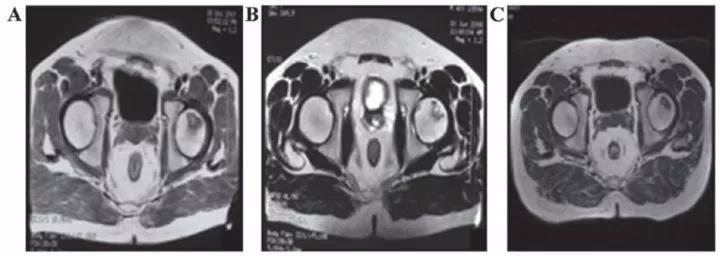

8、泌尿生殖系統(tǒng)疾病

? 勃起功能障礙

運用干細胞治療勃起功能障礙一方面可以完全取代受損和死亡的陰莖組織細胞,另一方面可以分泌一些因子修復功能受損的陰莖組織細胞。

丹麥15位勃起功能障礙患者在未接受藥物或陰莖移植術的情況下接受間充質干細胞的輸注,6個月后,8名男性能夠正常性交。